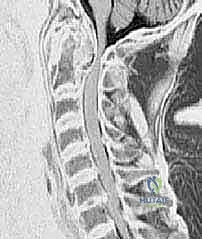

- التصوير المقطعي المحوسب (CT Scan) ثلاثي الأبعاد: وهو الفحص الأهم لتخطيط الجراحة. يعطي الدكتور هطيف خريطة دقيقة لتشريح العظام، حجم الكتل المفصلية، ومسار الشريان الفقري، مما يسمح له باختيار حجم ومسار المسامير بدقة المليمتر.

- التصوير بالرنين المغناطيسي (MRI): ضروري لتقييم حالة الحبل الشوكي، وجود أي كدمات أو تلف داخله، وتقييم حالة الأربطة (خاصة الرباط المستعرض).